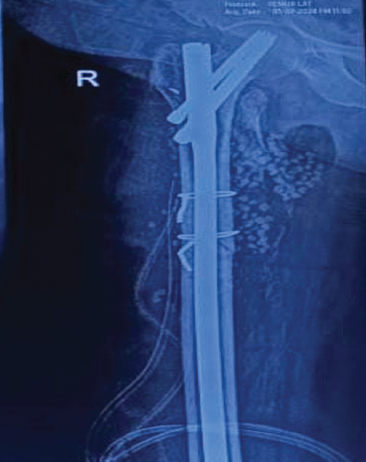

Removal of Hartshill Rectangle and Wires with Revision Pedicle Screw Fixation: Technical Challenges, Safety Considerations, and Clinical Outcomes in Complex Spinal Reconstruction – A Case Report

Ajay Kothari , Siddharth Aiyer , Parth K Shah , Parag Sancheti